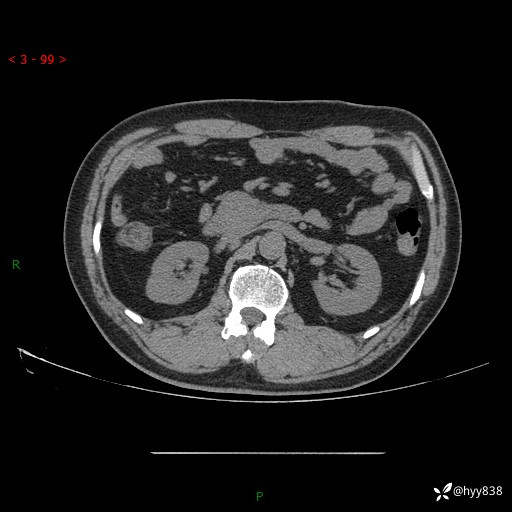

腹部CT平扫